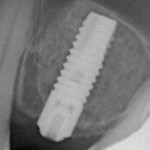

Собственно, результат такого подхода, несмотря на возражения Geistlich Pharma AG был очень даже ничего:

Так, что этот вариант заслуживает, если не активного внедрения, то, как минимум, внимания как со стороны производителя, так и со стороны имплантологов.